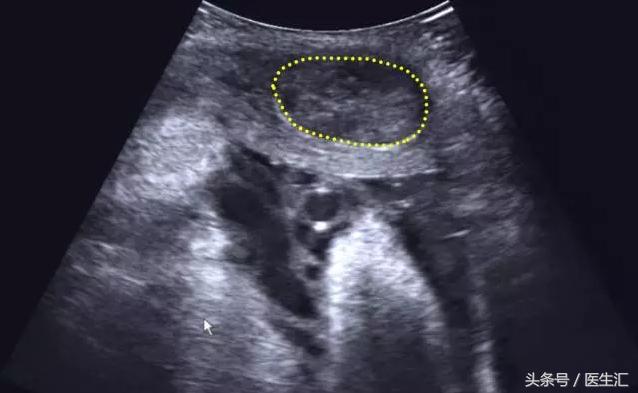

超声检查提示:宫底后壁胎盘与后壁肌层之间见混合回声区(超声表现1,见图1黄色圈内),与胎盘分界不清,范围约75mm×34mm,内回声不均匀,边缘及内部未见明显血流信号(检查要点1)。急诊剖宫产手术见胎盘80mm×50mm剥离面,占1/2(超过胎盘面积的1/3),宫腔积血约50ml,术后诊断胎盘早剥。

(图1)